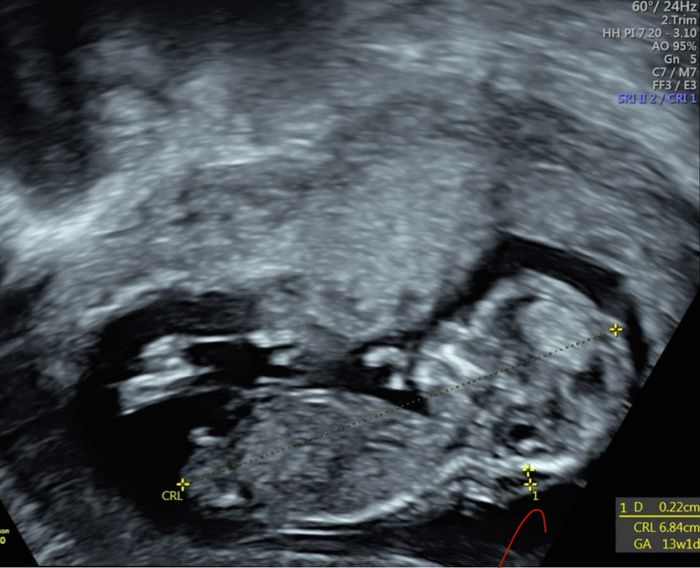

Ciao Sabrina! Non so se puoi aiutarmi perché credo che dalle immagini non si veda benissimo il tubercolo ma ecco sicuramente essendo più esperte di me può essere che mi sbaglio 🤣 ho fatto eco stamattina e in base alle sue misure dovrei essere 13+2 invece che 12+3. La ginecologa non è riuscita a sbilanciarsi, o meglio appena l’ha visto ha detto non saprei è ancora molto presto e può ancora cambiare, però così ti direi maschio. Poi appena ha cambiato posizione ha detto vedi in questa posizione ti avrei detto femmina. E in effetti in quella posizione si vedevano due lineette, mentre in altre un qualcosa che spunta 🤣 mi sono solo confusa di più le idee, ma comunque la mia sensazione è che sarà maschio. Ti lascio qualche eco espirando si capisca qualcosa Nub theory, giochiamo un po’ 4

In effetti dalla maggior parte delle eco sembra un maschietto. Solo in una ho il dubbio ma nelle altre il tubercolo mi sembra puntare molto in alto quindi in questo caso, direi maschietto anche io..

c’è anche una foto da sotto.. dove pare un maschietto a tutti gli effetti: altra possibilità sono i genitali gonfi per la femmina. Ma in quelle di profilo mi sembra puntare in su e se tracciò una linea tra tubercolo vescica e spina dorsale, l’angolo viene maschile. Fammi sapere!